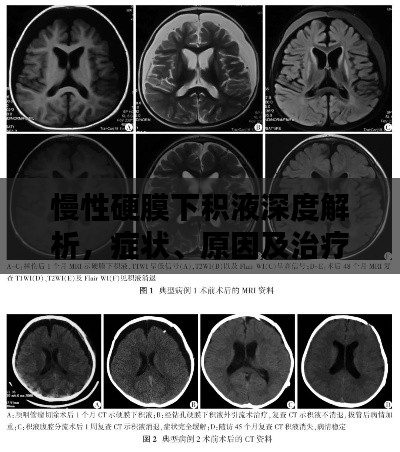

诊断与治疗

对于慢性硬膜下积液的诊断,通常需要进行头颅CT或MRI等影像学检查,治疗方法主要包括药物治疗和手术治疗,药物治疗主要是对症治疗,如使用脱水药物降低颅内压等,对于严重的慢性硬膜下积液,可能需要手术治疗以消除积液并恢复颅内压力平衡。